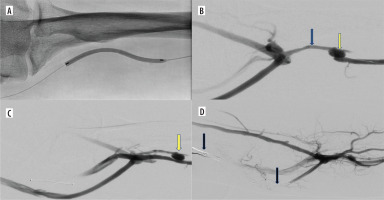

Figure 1

Endovascular creation of an arteriovenous fistula (endoAVF) in the radial vessels of the proximal forearm. A) Arteriography – vascular access via the radial artery at the wrist level (red arrow – radial artery). B) Phlebography – vascular access via the lateral radial vein at the wrist level (blue arrow – lateral radial vein). C) Electrodes positioned at the site of the anastomosis in proximal radial vessels (yellow arrow – electrodes in place of anastomosis). D) Arteriovenous fistula between radial artery and lateral radial vein (red arrow – radial artery, blue arrow – radial vein with vasospasm, yellow arrow – arterio-venous anastomosis)